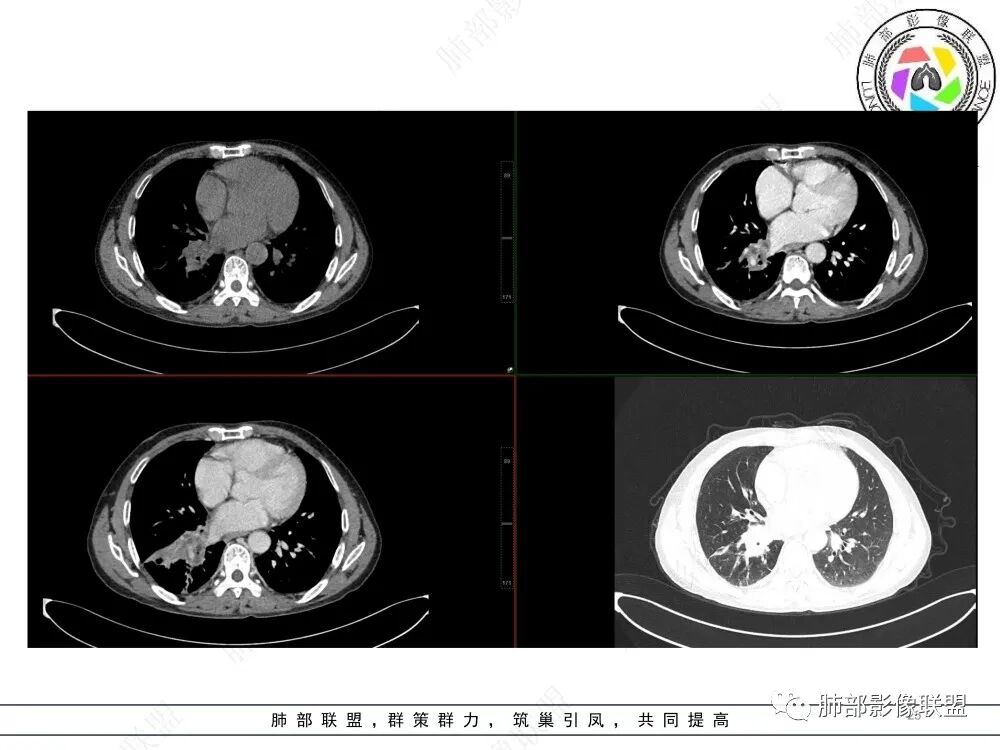

张思雨: 右肺下叶肺门处可见实性病变,包绕近端支气管,支气管堵塞,远端可见阻塞性肺不张,及多发指套征,增强扫描可见近端血管穿行,右侧胸水,纵膈多区淋巴结肿大,部分可见钙化灶,考虑:小细胞肺癌,腺癌,鳞癌,鉴别结核,淀粉样变。

秦化君:右肺自中间段支气管以下支气管狭窄,部分阻塞后扩张,周围软组织密度影围绕,密度不均,增强可见液化坏死,右下肺不张,右侧胸腔少量积液。结核先考虑。恶性肿瘤待排。

张欢:右肺下叶气管狭窄,可见阻塞性肺不张,密度不均,边界不清,有少量积液,考虑肺癌,鉴别结核。

魏俊明:单侧胸水,多发肿大淋巴结,强化均匀,右肺下叶支气管壁增厚,强化比较轻,恶性病变可能,首先考虑粘液表皮样癌。鉴别支气管内膜结核。

丽:老年男性,咳嗽,化验白细胞不高,右肺门增大,下叶支气管管腔变窄,见多发粘液栓形成,远端阻塞性肺不张,伴右侧胸腔少许积液,考虑鳞癌,鉴别结核。

1.老年男性患者,咳嗽、咳痰、胸痛2月余入院。既往病史不详。缺乏吸烟及粉尘接触史等。实验室检查C反应蛋白及降钙素原等升高。

2.CT影像右侧中间段及右肺下叶支气管阻塞、结节影突入,局部轻度强化,未见钙化。

3.右肺下叶呈实性高密度影,体积缩小,密度较均匀,强化明显(对比胸壁肌群),肺血管走行自如,偶见含气支气管。

4.右侧胸腔少量积液

5.右肺门增大,有肺门及纵隔见多处增大淋巴结。